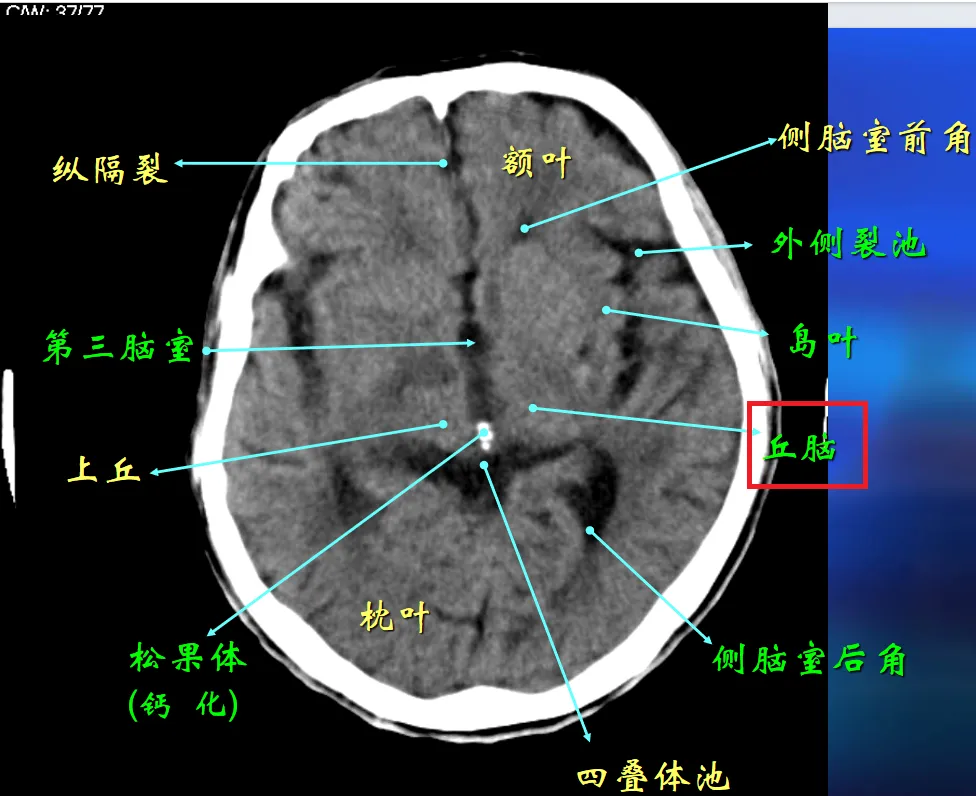

丘脑位置示意

位置深

丘脑是脑部较深在的区域,其前下方则毗邻下丘脑及中脑,约50%的丘脑表面被内囊所覆盖。手术难度较大,肿瘤切除时如损伤周围重要结构,将导致不良后果。

相邻器官重要

丘脑附近重要的邻居有松果体、下丘脑、中脑。

邻居二:中脑

中脑位于脑桥之上,恰好是整个脑的中点。中脑是视觉与听觉的反射中枢,凡是瞳孔、眼球、肌肉等活动,均受中脑的控制。生长的丘脑上的肿瘤,累及或者压迫丘脑的邻居们,一样会出现严重症状。